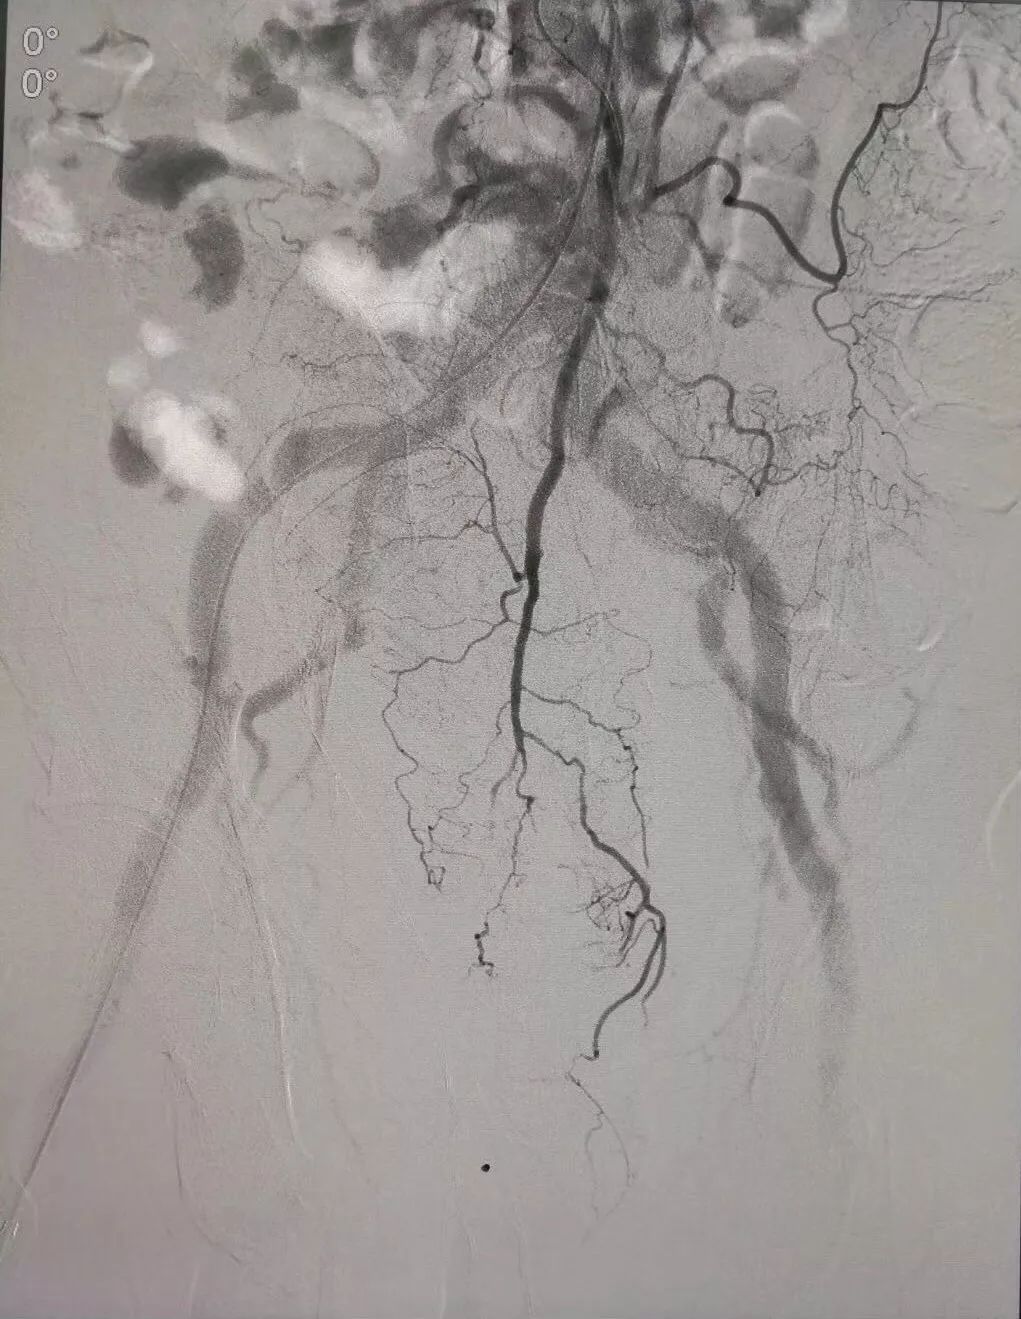

(术前DSA造影提示支气管动脉增粗、增多、絮乱,床表现为咯血,经久不愈)

(介入栓塞术后造影提示支气管动脉走向规则,清晰,术后咯血症状停止)